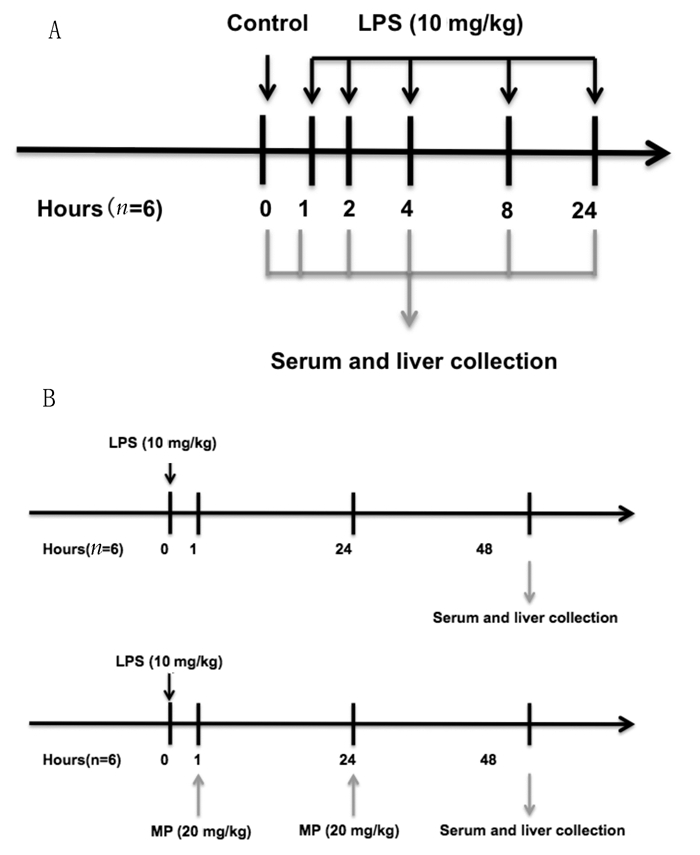

腹腔注射LPS制作小鼠内毒素血症肝损伤模型,制模条件参照李江等[8]实验方法。动物随机(随机数字法)分组:对照组(Control组),LPS组(LPS分别处理1、2、4、8、24、48 h后处死组),LPS+MP组(LPS处理1 h后腹腔注射MP组),每组6只。LPS组按腹腔注射LPS(10 mg/kg)后1、2、4、8、24、48 h经戊巴比妥麻醉后处死并收取血清及肝组织;LPS+MP组按照LPS(10 mg/kg)处理1h后腹腔注射MP[20 mg/(kg·d)],48 h经戊巴比妥麻醉后处死并收取血清及肝组织;健康对照组采用生理盐水处理;实验流程图见图 1。血清存放于-80℃冰箱,病理组织样本浸泡于4%多聚甲醛,肝组织经液氮瞬时冷冻后转移至-80℃冰箱,备用。

|

| 图 1 C57BL/6小鼠实验设计 Figure 1 Experimental design for C57BL/6 mice |